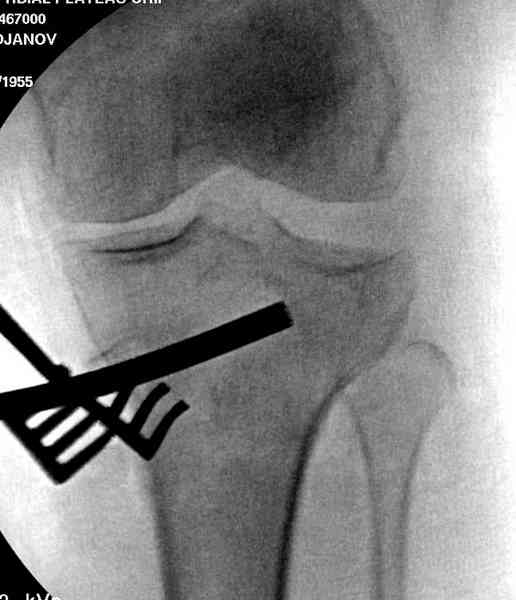

Медиально, обычно на протовоположной

строне, делается окно в кортикальном слое, кривым забойником под рентгеном поднимается импрессия.